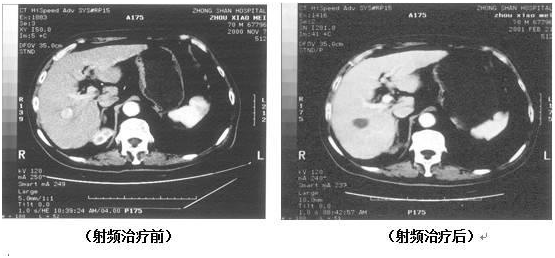

五、氩氦冷冻治疗

(男性,69岁,右肺鳞癌)

通过氩气的快速降温在胞内形成冰球,维持10-15分钟后用氦气进行升温,利用热胀冷缩的原理使肿瘤细胞破裂,从而达到治疗效果。适用范围:

肝癌、胰腺癌、直肠肛管癌、肺癌、肾癌、膀胱癌、前列腺癌、子宫癌、子宫肌瘤、卵巢癌、脑膜瘤、脑胶质瘤、神经纤维瘤、脊索瘤、骨或脊柱的良、恶性肿瘤、乳腺癌、乳腺纤维瘤、皮肤癌、鼻咽癌、甲状腺癌及癌症止痛。